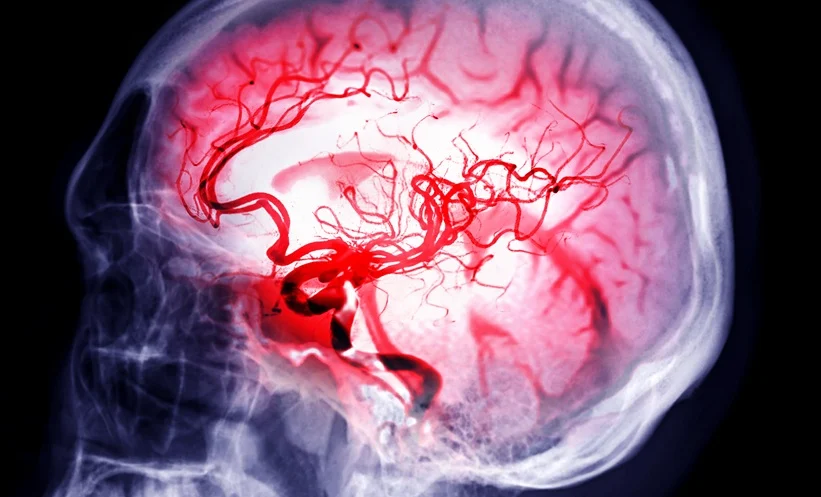

GLP-1RAs Linked to Reduced Haemorrhagic Stroke Risk

GLP-1RAs Linked to Reduced Haemorrhagic Stroke Risk: Glucagon-like peptide-1 receptor agonists (GLP-1RAs), a widely prescribed class of medications for type 2 diabetes, are gaining attention for benefits beyond glycaemic control. A 2026 retrospective cohort study has found that GLP-1RA prescriptions are associated with a reduced risk of aneurysmal rupture in patients living with type 2 … Read more